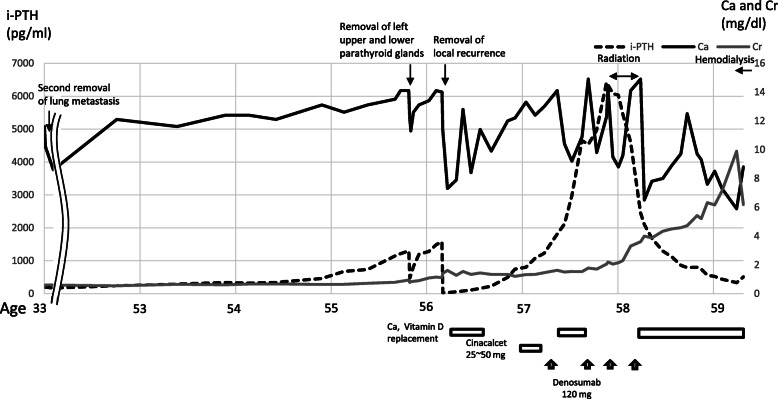

Fig. 2.

Blood test results and progress of treatment